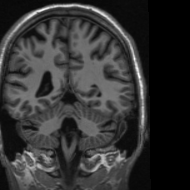

In addition, we provide the visualization results of some selected MR images reconstructed by the state-of-the-art ISTA-Net+ [33] and our proposed ResGD-Net on compressive sensing (CS) ratio 10%percent1010\%, 20%percent2020\% and 30%percent3030\%. The results are evaluated under metrics the Peak Signal-to-Noise Ratio (PSNR), the Structural Similarity (SSIM) and the Mean Squared Error (MSE). For better visualization, we rescale the pixel value by multiplying 8.0×8.0\times on the error maps (the second row of Figs. 5 - 7) when displaying.

Refer to caption

(a) ISTA-Net+

PSNR: 35.7335.7335.73dB

SSIM: 0.95640.95640.9564

MSE: 2.671e42.671𝑒42.671e-4

(b) ResGD-Net

PSNR: 41.3141.3141.31dB

SSIM: 0.97720.97720.9772

MSE: 7.385e57.385𝑒57.385e-5

(c) True

Figure 7: Reconstruction results of a brain MR image [3] with radial mask of CS ratio 30% using the state-of-the-art ISTA-Net+ [33] and the proposed ResGD-Net. The figures in the second row are the difference images compared to the true image